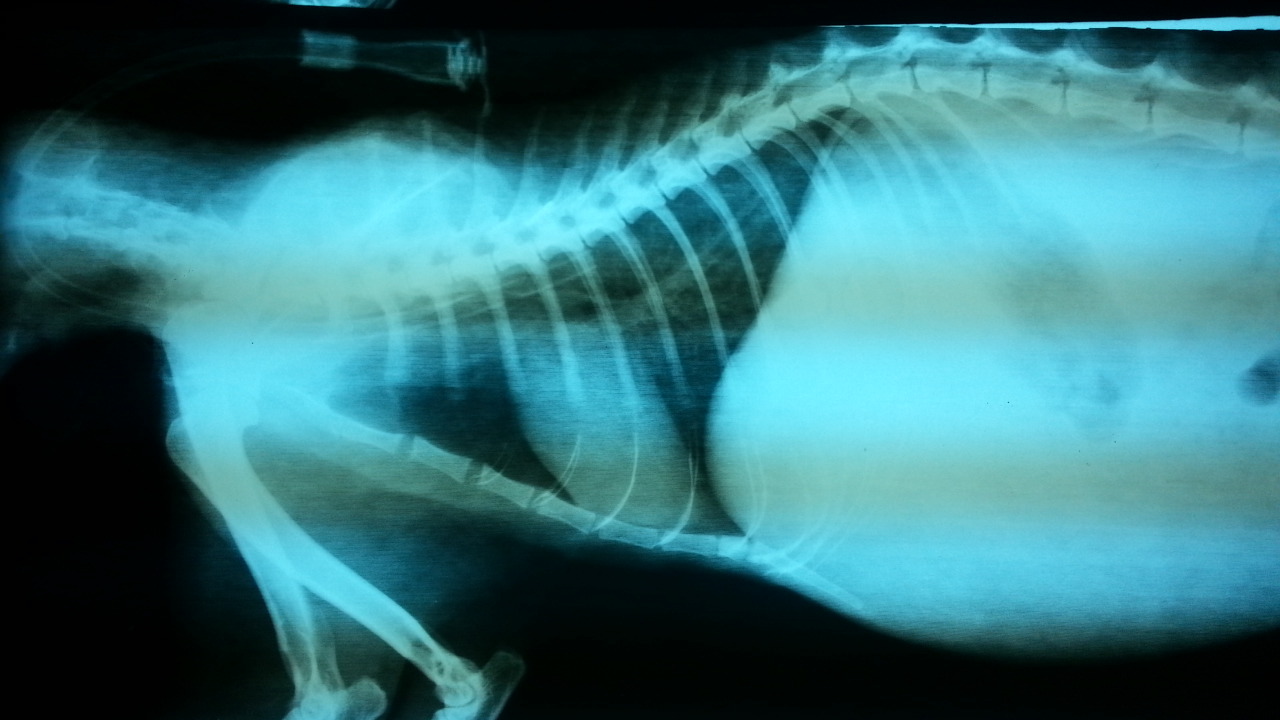

主題: 被遺棄路倒街頭的撒嬌貓 申請者姓名: 岳丹楓 花色: 申請日期: 2012-11-21 16:43:12 申請者部落格: 申請者臉書網址: http://www.facebook.com/media/set/?set=a.429066957129475.85858.186574344712072&type=3 所在縣市/合作醫院: 台北市/澄毅動物醫院 治療費用: 79300元 需求人數: 81人 已結案 (2013-06-27 14:04:59) 報名人員: 以四面佛名義迴向阿咪,咪仔(已付款)、以四面佛名義迴向阿咪.咪仔(已付款)、以四面佛名義迴向阿咪.咪仔(已付款)、以四面佛名義迴向阿咪.咪仔(已付款)、以四面佛名義迴向阿咪.咪仔(已付款)、以四面佛名義迴向阿咪.咪仔(已付款)、陳小茜(已付款)、阿兔仔(已付款)、iMADOKA(已付款)、Gracelyann、wowjill(已付款)、Clio Chen(已付款)、懂懂沒(已付款)、Karen Huang(已付款)、meemee(已付款)、朱苓雪、林螢逸(已付款)、Alexandria Chuko、cats800tw(已付款)、陳冰冰(已付款)、裘裘(已付款)、Dana Hsu(已付款)、Michelle(已付款)、WeiLin Chen(已付款)、philip(已付款)、燕蔓琦(已付款)、Ping Meng(已付款)、Claire Chen(已付款)、Sky(已付款)、Sky(已付款)、Sky(已付款)、Sky(已付款)、Sky(已付款)、Sky(已付款)、Sky(已付款)、Sky(已付款)、Sky(已付款)、Sky(已付款)、Sky(已付款)、Sky(已付款)、Sky(已付款)、Sky(已付款)、Sky(已付款)、Sky(已付款)、Sky(已付款)、Sky(已付款)、Sky(已付款)、Sky(已付款)、Sky(已付款)、Sky(已付款)、Sky(已付款)、Sky(已付款)、Sky(已付款)、Sky(已付款)、Sky(已付款)、Sky(已付款)、Sky(已付款)、Sky(已付款)、Sky(已付款)、Sky(已付款)、Sky(已付款)、Sky(已付款)、Sky(已付款)、Sky(已付款)、Sky(已付款)、Sky(已付款)、Sky(已付款)、Sky(已付款)、Sky(已付款)、Sky(已付款)、Sky(已付款)、Sky(已付款)、Sky(已付款)、Sky(已付款)、Sky(已付款)、Sky(已付款)、Sky(已付款)、Sky(已付款)、Sky(已付款)、Sky(已付款)、Sky(已付款)、Chen Ping(已付款)、Ugene Wu(已付款)、Li Li Hsieh(已付款)、 候補人員: Bella、 動物病情說明: 喵咪原本是有家的,但逃家後主人不願再把牠帶回照顧,牠就獨立在通安街附近生活,平時會有餵養牠的愛媽和居民,但前陣子照顧牠的愛媽發現牠似乎不太對勁,試著投藥治療,情況卻時好時壞,最後已經不願意吃飯,虛弱,緊急進醫院做治療,初步外觀檢查懷疑是口齦炎在做怪,沒想到經過檢驗後發現是嚴重貧血需立即輸血。

在等待輸血前,藉由鼻胃管灌食及代用血漿維持基本能量,在愛心媽媽及民眾愛心轉貼緊急輸血公告後,喵咪總共成功的輸血了5次。

在首次輸血後,喵咪情況有明顯好轉,也願意自己吃飯,但血液數值還不到正常值,需要再次輸血。 住院期間喵咪有強大的意志力,即便瘦弱的身軀連站起都很費力,也還是會努力的跟醫師們撒嬌討關愛。

住院期間經歷了呼吸道感染、脹氣、下痢等等。醫師則每日輪班的用針筒餵食,

但等待第3次輸血時,情況又轉壞,不願意進食,最後只好插食道胃管灌時維持牠一天的能量來源。最後第5次輸血後發現血液的供給以無法提供喵咪身體消耗的速度,情況急轉直下,前後經過41天的治療後還是無法敵過病魔而往生了。